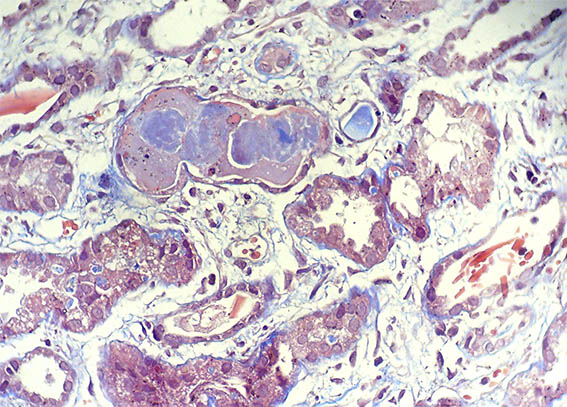

Figura 7.

Tricrómico de Masson, X400.

Figura 8.

PAS, X400.